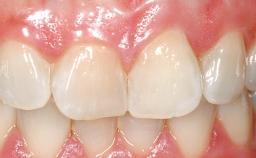

A 36-year-old female patient was referred for the replacement of the upper left central incisor (tooth 21), which had fractured. Although the tooth had been asymptomatic for many years, the crown began to loosen, at which time she presented to her dentist for an assessment. Teeth 21 and 22 had both been endodontically treated many years previously. She was a healthy individual and a non-smoker.

On examination, the patient had a low lip line and only displayed the coronal half of the anterior teeth when smiling.

The crown of tooth 21 was splinted to the adjacent teeth with composite resin, and the gingiva was inflamed.